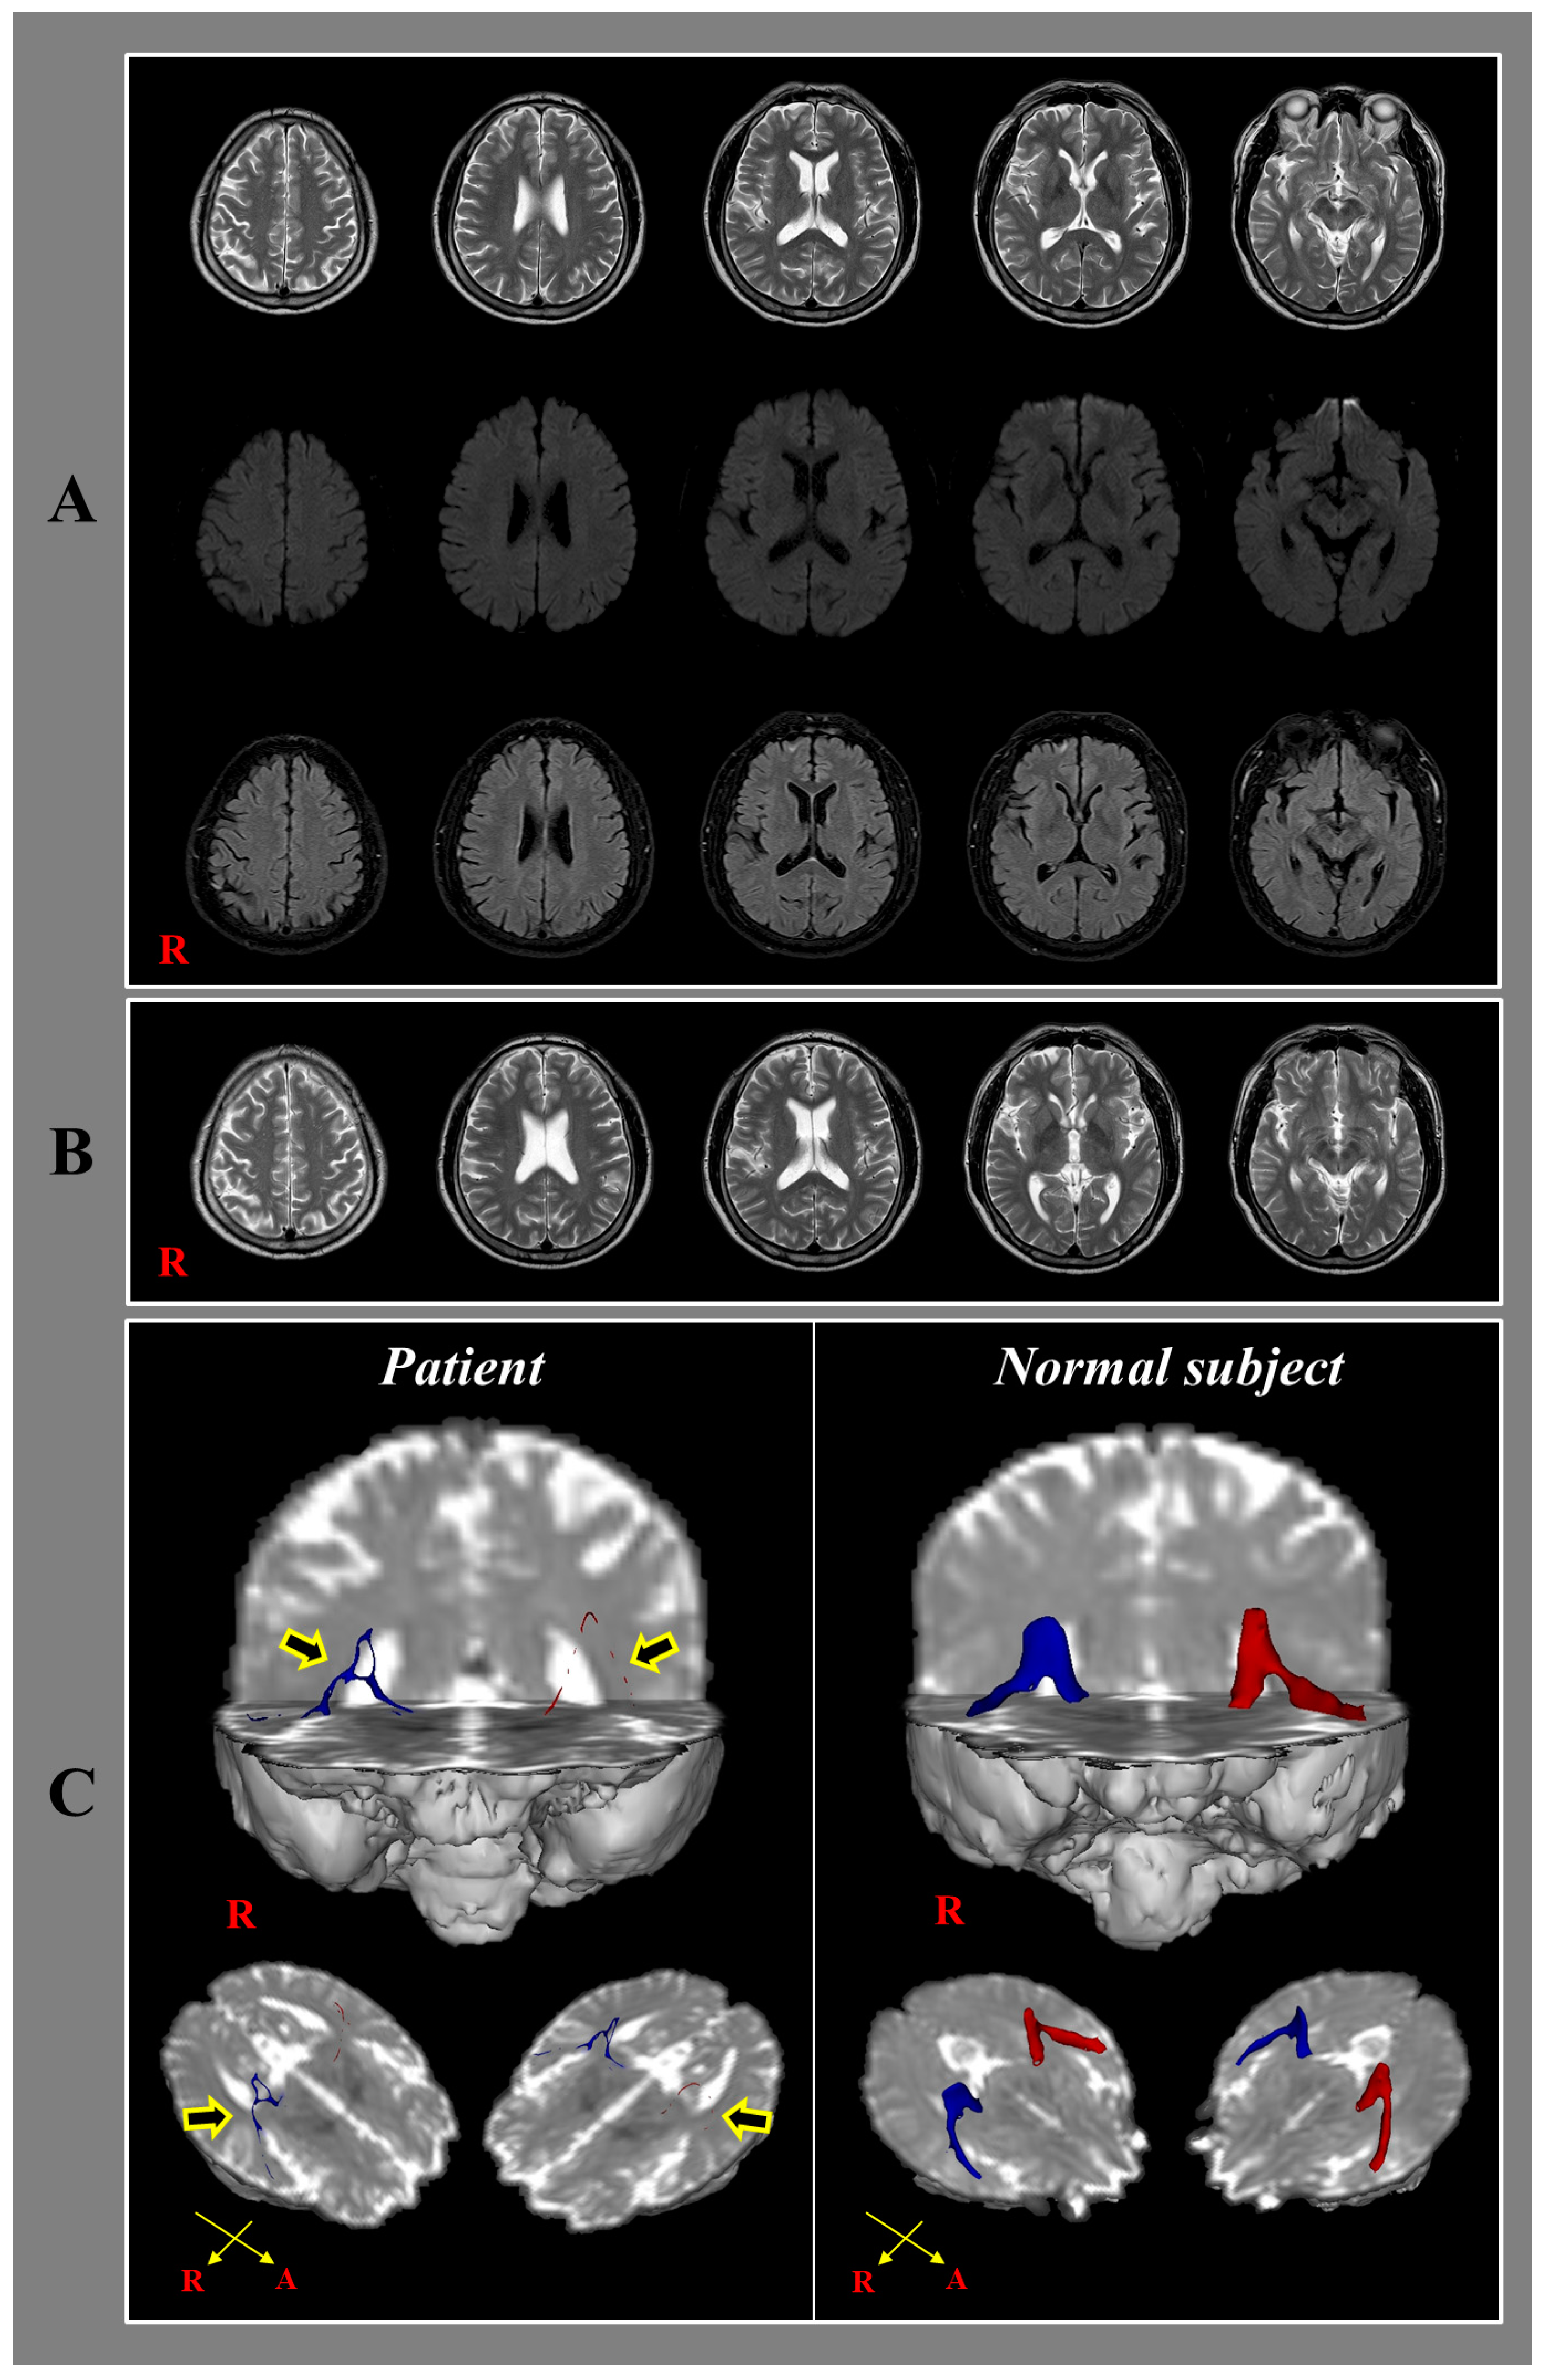

Diffusion Tensor Tractography